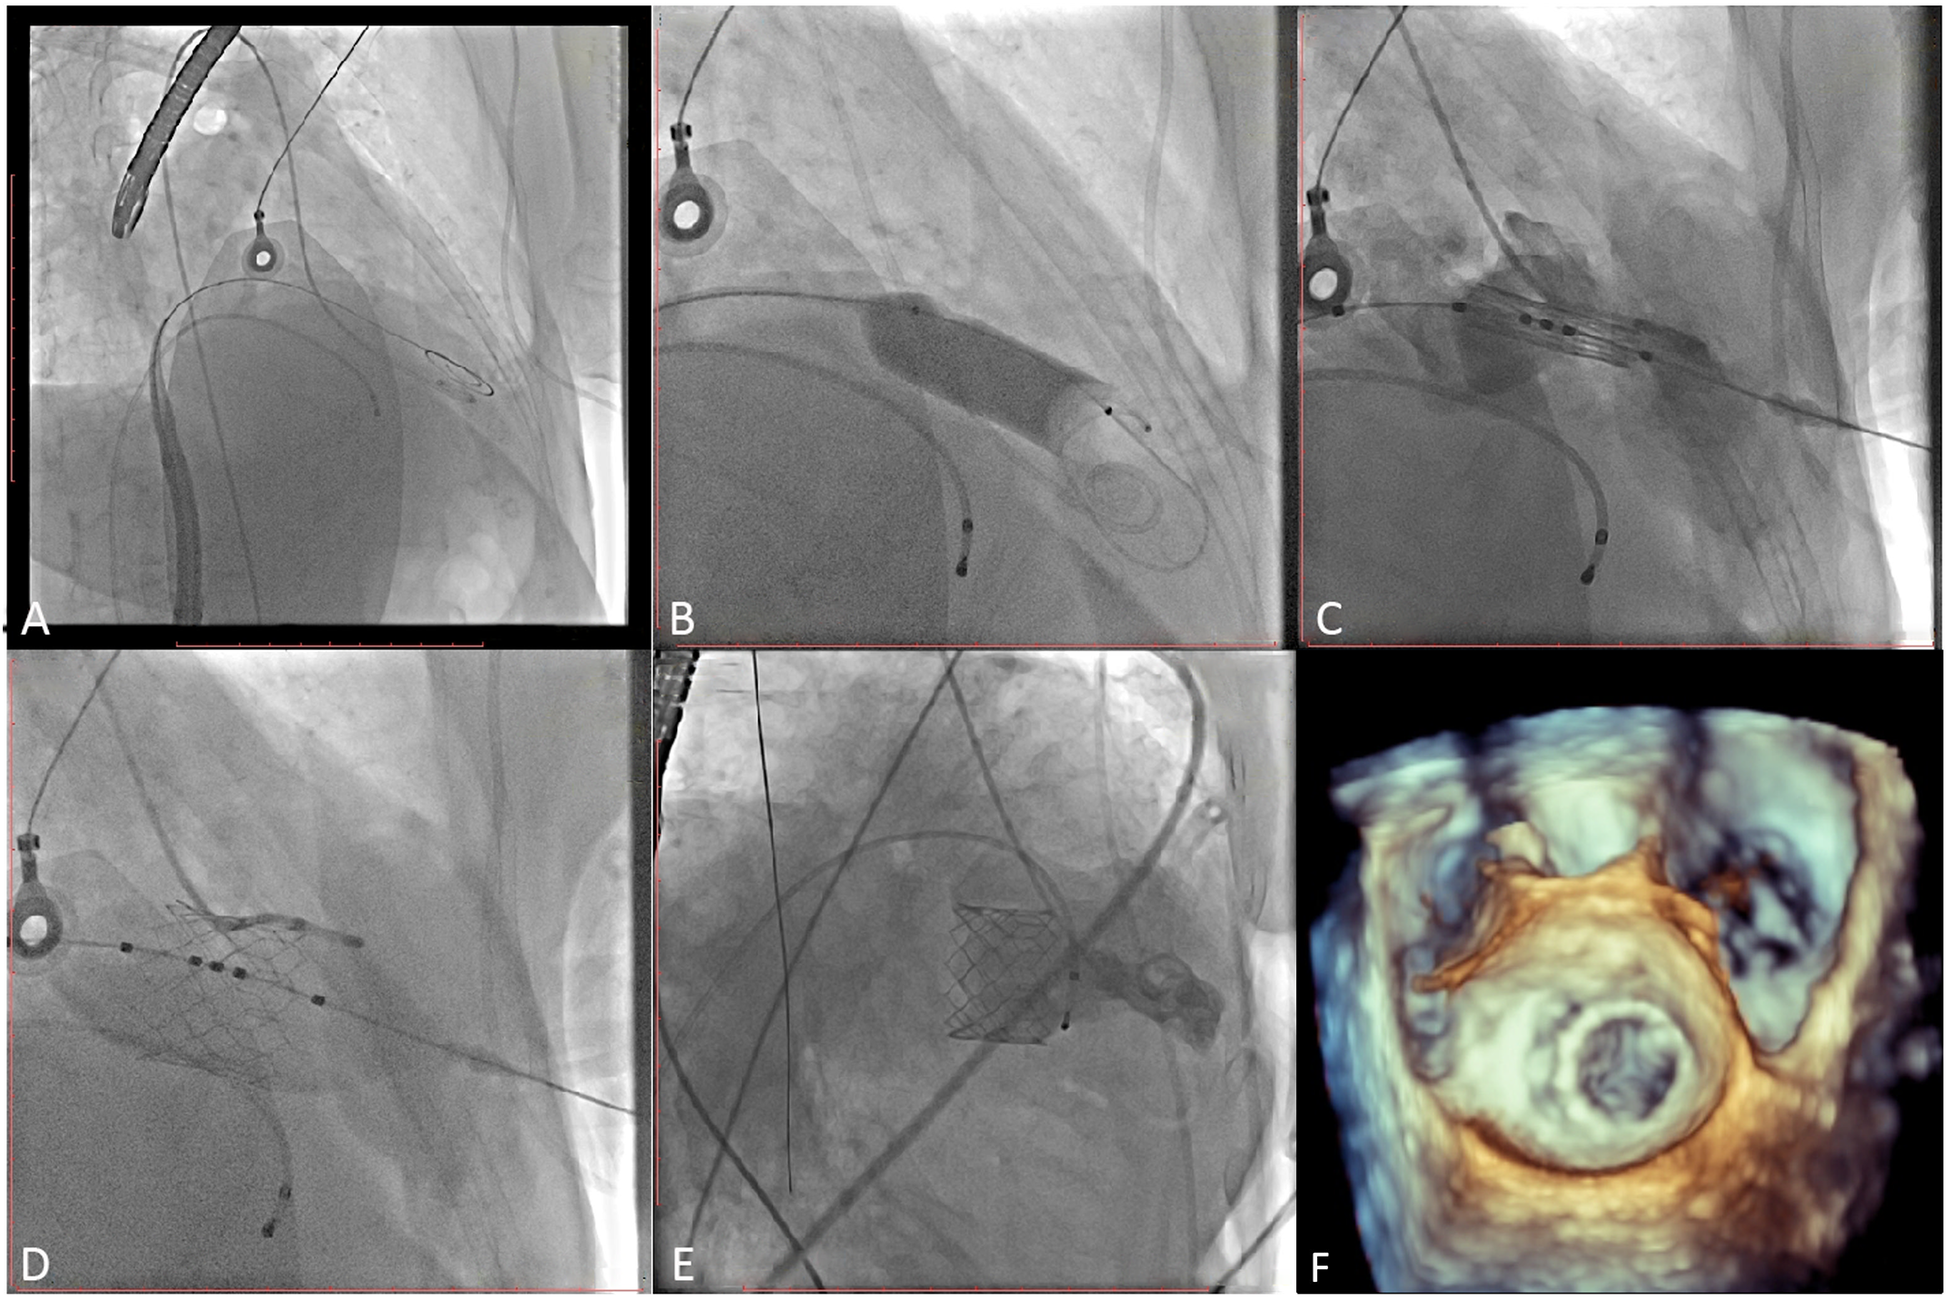

The patient's bilateral femoral artery region was disinfected; the right femoral vein was selected as the puncture point; and the patient was anesthetized with 2 ml of 2% lidocaine administered via local infiltration. After a successful puncture, a 5 Fr arterial sheath tube was placed, and 3,000 units of heparin was injected intravenously. A 6F sheath tube was inserted through the right common jugular vein and the pacemaker catheter was sent to columnae cordis of right ventricle. Subsequently, a 6 Fr sheath was used to lead the 1.5 m Superstiff guide wire (Boston Science Co. Ltd., Boston, USA) to the left atrium through the atrial septal puncture, and the 6 Fr pigtail catheter was inserted to the left ventricle through the guide wire under digital subtraction angiography (DSA) guidance (Figures 3A,B; Supplementary Videos 1, 2). Then, the mitral annulus was marked, and the Prizvalve delivery system was implanted via the guide wire. Pacing to 180 beats/min, and the Prizvalve prothesis was gradually released (Figure 3C; Supplementary Video 3). After the release was completed (Figure 3D; Supplementary Video 4), DSA (Figure 3E; Supplementary Video 5) and transesophageal echocardiography (TEE) (Figure 3F; Supplementary Video 6) showed that the prosthesis was well fixed without regurgitation or paravalvular leakage (PVL).

Figure 3

Procedural details. (A) The pigtail catheter was inserted into the left ventricle. (B) Pre-dilation was used before delivery system insertion. (C) The prothesis was positioned at mitral valve. (D) The prosthesis was completed release and post-dilation. (E, F) Digital subtracted angiography and transesophageal echocardiography displayed the good position and function of the prosthesis.